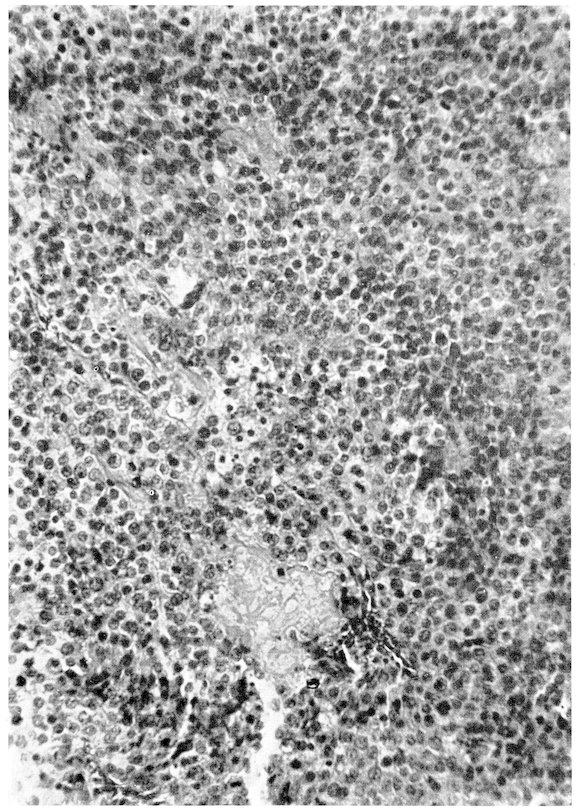

Columbæ:

Columbidæ:

Ocyphaps lophotes,